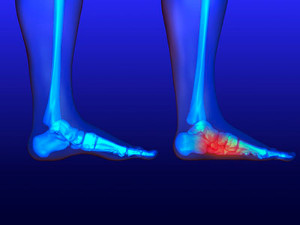

The plantar fascia is a connective tissue in the heel that stretches across the bottom length of your foot. Plantar fasciitis occurs when the connective tissue becomes inflamed, causing heel pain and discomfort during physical activity. Although the condition is completely treatable, traditional methods can take up to a year to start becoming effective.

Plantar fasciitis is caused by a number of everyday activities, so understanding the condition is important for managing and treating it. One of the most common causes of plantar fasciitis is excessive running, especially with improper fitting or non-supportive shoes. Too much exercise can lead to the plantar fascia being overworked and overstretched, which can cause tears in the tissue. Along with improper fitting shoes, pronation, the rolling of the feet inward, is a common cause of plantar fasciitis. If not treated properly, the plantar fascia becomes overstretched and starts to tear, causing inflammation.

Causes of Heel Pain

Heel pain can be debilitating and can form due to a variety of reasons. The most common cause of heel pain occurs when the band of tissue that connects the heel bone to the toes, known as the plantar fascia, becomes inflamed causing plantar fasciitis. When the Achilles tendon becomes inflamed Achilles tendonitis may occur, and this can lead to heel pain too. Heel pain can also be caused by a natural wearing of the fat pad which is connected to the heel, as well as stress fractures, bursitis, or a variety of diseases such as arthritis and gout. If you are suffering from heel pain it is highly recommended that you visit a podiatrist who can determine what the cause of your pain is. A podiatrist will be able to provide a proper treatment plan for your heel pain as well.

Heel pain can be debilitating and can form due to a variety of reasons. The most common cause of heel pain occurs when the band of tissue that connects the heel bone to the toes, known as the plantar fascia, becomes inflamed causing plantar fasciitis. When the Achilles tendon becomes inflamed Achilles tendonitis may occur, and this can lead to heel pain too. Heel pain can also be caused by a natural wearing of the fat pad which is connected to the heel, as well as stress fractures, bursitis, or a variety of diseases such as arthritis and gout. If you are suffering from heel pain it is highly recommended that you visit a podiatrist who can determine what the cause of your pain is. A podiatrist will be able to provide a proper treatment plan for your heel pain as well.

Heel pain is often associated with plantar fasciitis. The plantar fascia is a band of tissues that extends along the bottom of the foot. A rip or tear in this ligament can cause inflammation of the tissue.

Heel spurs are another cause of pain. When the tissues of the plantar fascia undergo a great deal of stress, it can lead to ligament separation from the heel bone, causing heel spurs.

The plantar fascia is the fibrous tissue that runs along the bottom of the foot and connects to the heel bone. When the plantar fascia becomes inflamed due to overstretching, plantar fasciitis occurs and usually results in heel pain, heel spurs, or arch pain. Pain is often felt on the inside of the foot where the heel and arch meet, and it is at its worst in the mornings or after a long rest. Flat feet is the leading cause of plantar fasciitis because the plantar fascia gets stretched away from the heel when bearing weight. When flat feet are the cause of plantar fasciitis, orthotics that support the arch will likely be needed for treatment. Since plantar fasciitis has other causes, patients who believe that they have it should consult with a podiatrist to find the cause and a proper treatment method.

The plantar fascia is the fibrous tissue that runs along the bottom of the foot and connects to the heel bone. When the plantar fascia becomes inflamed due to overstretching, plantar fasciitis occurs and usually results in heel pain, heel spurs, or arch pain. Pain is often felt on the inside of the foot where the heel and arch meet, and it is at its worst in the mornings or after a long rest. Flat feet is the leading cause of plantar fasciitis because the plantar fascia gets stretched away from the heel when bearing weight. When flat feet are the cause of plantar fasciitis, orthotics that support the arch will likely be needed for treatment. Since plantar fasciitis has other causes, patients who believe that they have it should consult with a podiatrist to find the cause and a proper treatment method.

What Is Plantar Fasciitis?

Plantar fasciitis is the inflammation of the thick band of tissue that runs along the bottom of your foot, known as the plantar fascia, and causes mild to severe heel pain.

The plantar fascia is a connective tissue in the heel that stretches across the bottom length of your foot. Plantar fasciitis occurs when the connective tissue becomes inflamed, causing heel pain and discomfort during physical activity. Although the condition is completely treatable, traditional methods can take up to a year to start becoming effective.

Plantar fasciitis is caused by a number of everyday activities, so understanding the condition is important for managing and treating it. One of the most common causes of plantar fasciitis is excessive running, especially with improper fitting or non-supportive shoes. Too much exercise can lead to the plantar fascia being overworked and overstretched, which can cause tears in the tissue. Along with improper fitting shoes, pronation, the rolling of the feet inward, is a common cause of plantar fasciitis. If not treated properly, the plantar fascia becomes overstretched and starts to tear, causing inflammation.